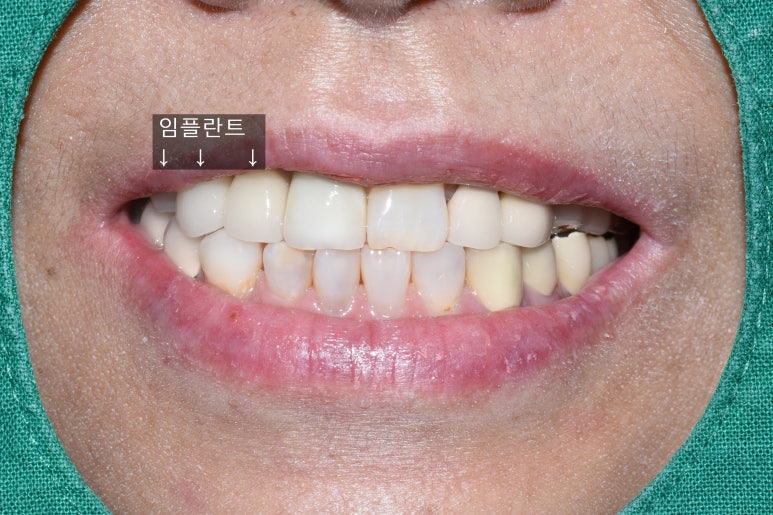

기존의 다른 치아와 다른 임플란트, 보철물과 조화를 이루는 앞니 임플란트

화살표 표시한 부분내의 치아가 이번에 진행한 임플란트입니다.